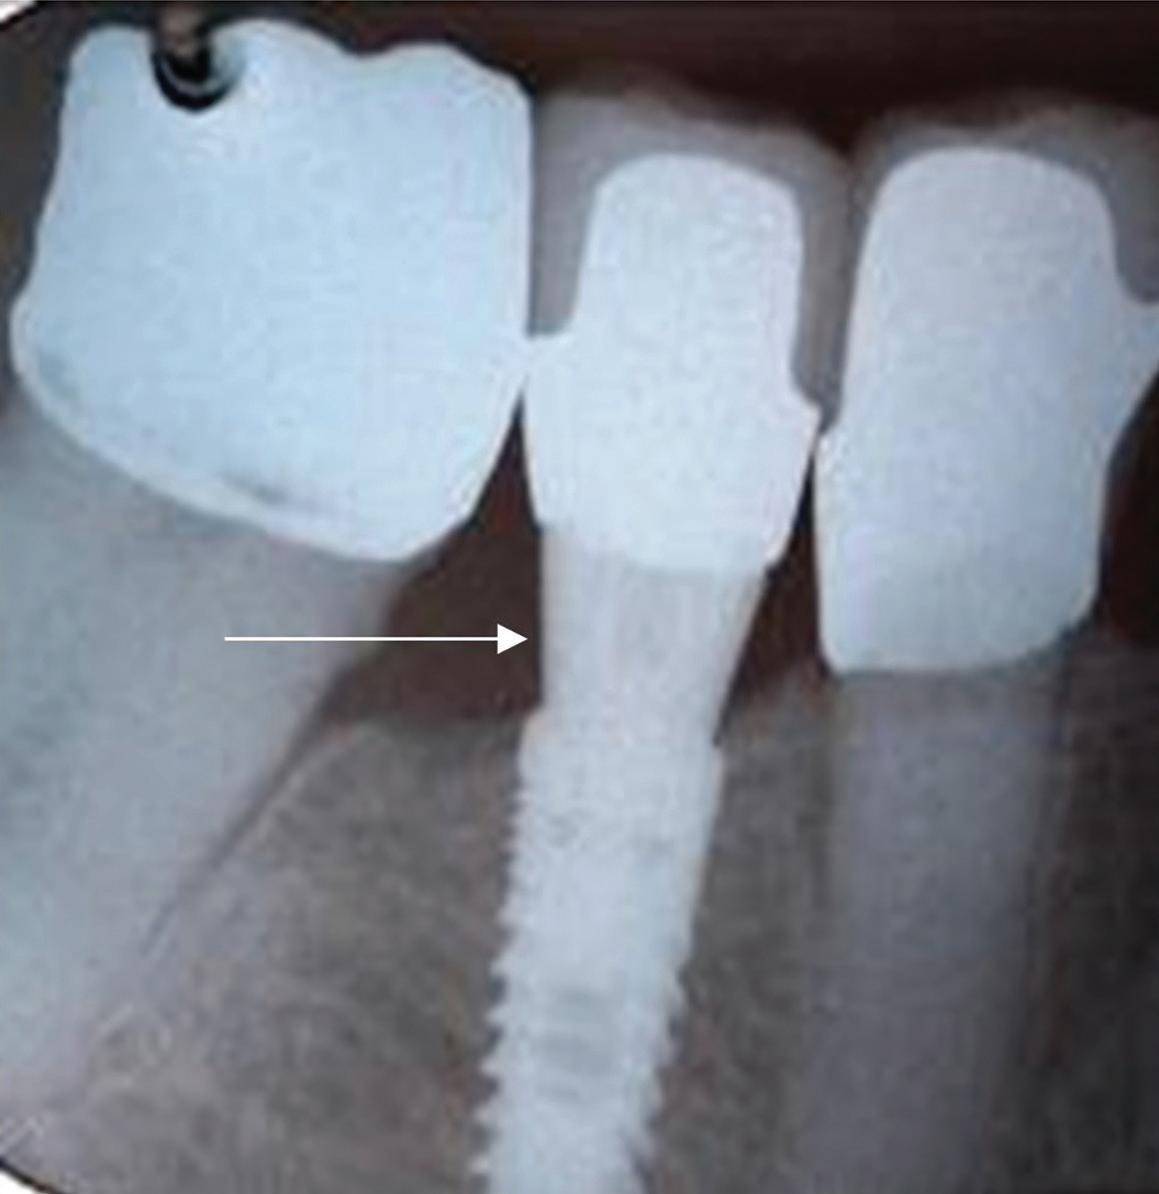

When a surgical guide is used, the first drill used is the pilot drill. It is inserted into the guide and used to full depth of the guide per the digital planning. A periapical radiograph is taken to ensure that the orientation and depth are consistent with the preoperative planning. If everything looks aligned, the drill sequence is continued stepwise, sizing the osteotomy appropriately for the case. I have never used a guide that did not seat, but verification radiographs are still taken as a precaution. When implants are placed in a guided procedure, after the radiograph of the pilot drill at depth is taken, no other radiographs are taken until after the implant is placed.

If no perforation is present, the implant is placed in the ideal positioning determined from the preoperative planning (Fig 7). The implant handpiece is preferred for placing the implant fixture because it provides a torque reading in real time as the implant is being placed. The implant motor is electively set to 35 N/cm, and the handpiece will stop advancing the implant once it reaches that reading. The hand driver is then used to finish fully seating the implant at

Fig 7. The implant positioning confirms excellent buccal bone width that will promote long-term stability.